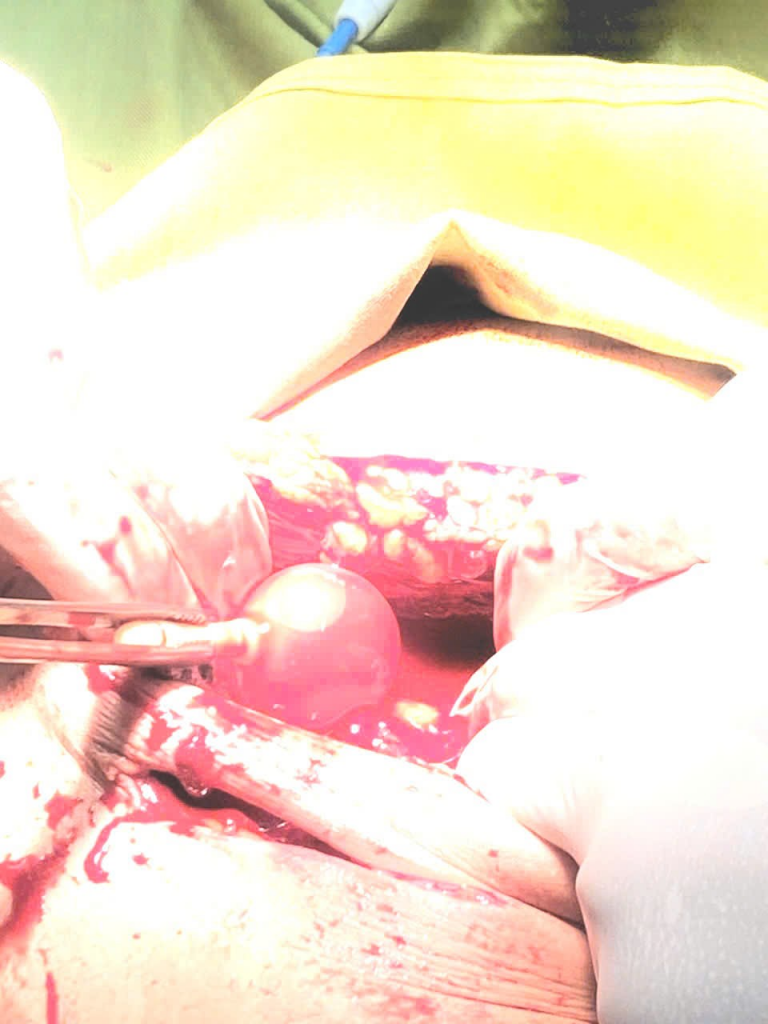

Ngày 24/7/2025, Trung tâm Y tế Than Uyên tiếp nhận bệnh nhân L.T.Y, 28 tuổi, sống tại xã Mường Than, tỉnh Lai Châu nhập viện do bị trượt ngã, cành cây chọc vào bụng. Các bác sỹ đã lập tức hội chẩn ca bệnh vết thương thấu bụng phức tạp, tiến hành mổ cấp cứu, khâu bàng quang bị vỡ (khoảng 10cm), đặt sonde dẫn lưu nước tiểu. Sau hơn 2 giờ phẫu thuật, cấp cứu, bằng sự nổ lực của ekip thầy thuốc, ca phẫu thành công tốt đẹp, sức khỏe bệnh nhân đã dần ổn định trong sự vui mừng của bệnh nhân, thân nhân và các thầy thuốc. Trung tâm Y tế Than Uyên khuyến cáo nhân dân hết sức cẩn thận khi lao động, đề phòng chấn thương, nhất là trong mùa mưa bão!

Một số hình ảnh ca phẫu thuật: